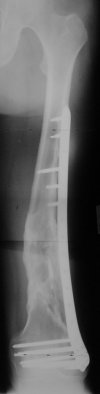

KEMMD> method of treatment for distal femur fractures

A new toy is more interesting and fashionable. And anyway it is not panacea, i have already seen presentations with LISS failures like the attached one presented by D.Seligson. And people also demonstrated incisions say that the method is not so LESS invasive as it supposed to be.